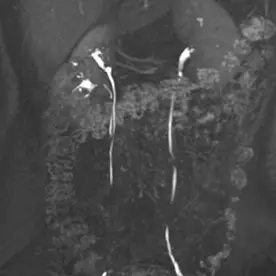

Es erfolgte eine MRT der Nieren mit intravenöser Kontrastmittelgabe und urographischer Phase zur dedizierten Darstellung der ableitenden Harnwege. Es bestätigte sich eine Anlagevariante der rechten ableitenden Harnwege, eine Doppelung des rechten proximalen Ureters mit Fusion im proximalen Drittel (Ureter fissus) bei regelrechter Darstellung der Nierenbeckenkelchsysteme (Bild 1). Im Nierenparenchym beidseits zeigen sich mehrere, keilförmige Areale mit Diffusionsstörungen und teils T2-hyperintensen Foci (Bild 2 und 3). Nach i.v. Kontrastmittelgabe zeigt sich ein weitesgehend unauffällig und homogen kontrastiertes Nierenparenchym beidseits (Bild 4).

Bild einer chronischen Pyelonephritis i.R. einer rezidivierender Reflux auf dem Boden eines Ureter fissus.